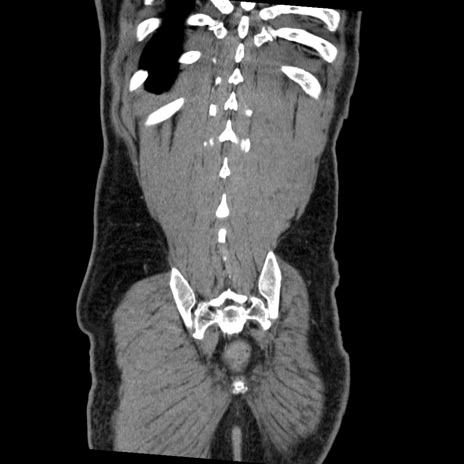

症例22(冠状断像)

【症例】50歳代男性

【主訴】腹痛

【現病歴】AVMからの被殻出血のため回復期リハ病棟入院中。 本日午後3時頃急に下腹部痛が出現した。

【既往歴】AVM、被殻出血、虫垂炎、高血圧

【身体所見】意識晴明、左半身不全麻痺、会話の理解は良好、36.5°C、腹部:膨隆、全体に板状硬、下腹部正中に圧痛点あり、反跳痛-、筋性防御不明、右下腹部にope scar

【データ】WBC 9400、CRP 0.06